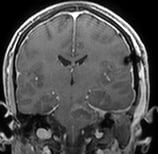

Ressonância coronal mostrando volumoso cavernoma (seta) na ponte (tronco encefálico).